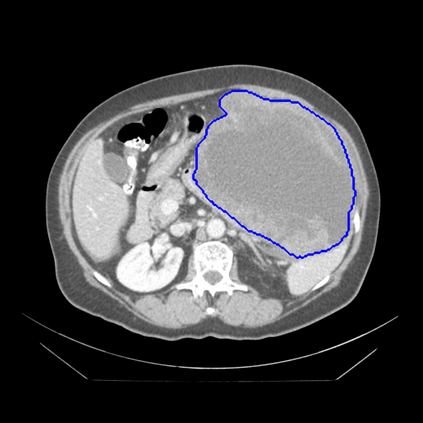

Radiomics uses quantitative medical imaging features to predict clinical outcomes. Currently, in a new clinical application, finding the optimal radiomics method out of the wide range of available options has to be done manually through a heuristic trial-and-error process. In this study we propose a framework for automatically optimizing the construction of radiomics workflows per application. To this end, we formulate radiomics as a modular workflow and include a large collection of common algorithms for each component. To optimize the workflow per application, we employ automated machine learning using a random search and ensembling. We evaluate our method in twelve different clinical applications, resulting in the following area under the curves: 1) liposarcoma (0.83); 2) desmoid-type fibromatosis (0.82); 3) primary liver tumors (0.80); 4) gastrointestinal stromal tumors (0.77); 5) colorectal liver metastases (0.61); 6) melanoma metastases (0.45); 7) hepatocellular carcinoma (0.75); 8) mesenteric fibrosis (0.80); 9) prostate cancer (0.72); 10) glioma (0.71); 11) Alzheimer's disease (0.87); and 12) head and neck cancer (0.84). We show that our framework has a competitive performance compared human experts, outperforms a radiomics baseline, and performs similar or superior to Bayesian optimization and more advanced ensemble approaches. Concluding, our method fully automatically optimizes the construction of radiomics workflows, thereby streamlining the search for radiomics biomarkers in new applications. To facilitate reproducibility and future research, we publicly release six datasets, the software implementation of our framework, and the code to reproduce this study.

翻译:放射科使用定量医学成像特征来预测临床结果。目前,在一个新的临床应用中,通过一个超常试验和高压过程,通过人工操作,从广泛的现有选项中找到最佳放射法。在本研究中,我们提议了一个框架,自动优化每个应用程序的放射工作流程的建设。为此,我们将放射作为模块工作流程,并包括每个部件的大量通用算法。为了优化每个应用程序的工作流程,我们使用随机搜索和聚合的自动机学习方法。我们用12种不同的临床应用来评估我们的方法,结果在曲线下应用的以下领域:1) 脂色瘤(0.83);2) 脱氧型纤维瘤(0.82);3 初级肝脏肿瘤(0.80);4 气肠肿瘤(0.77)、5 彩虹肝脏移植(0.61); 6 脑膜细胞变异常(0.45); 7) 肝细胞变异常(0.8) 脑纤维变异位(0.80); 9) 直径直线型癌症(0.74) 和头型癌症(0.77) 直径研究(10) 。